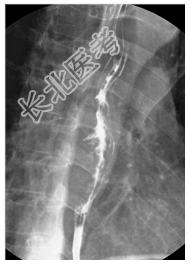

- [材料题] 病历摘要:男,70岁。因剑突下疼痛伴吞咽异物感2月来诊。查体:无特殊。给予食道吞钡检查。

- 简答题1、诊断及依据是什么?

- 简答题2、鉴别诊断有哪些?